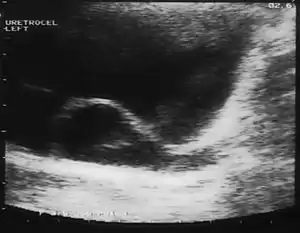

Ureterocele

A ureterocele is a congenital abnormality found in the ureter. In this condition the distal ureter balloons at its opening into the bladder, forming a sac-like pouch. It is most often associated with a duplicated collection system, where two ureters drain their respective kidney instead of one. Simple ureterocele, where the condition involves only a single ureter, represents only twenty percent of cases.

Since the advent of the ultrasound, most ureteroceles are diagnosed prenatally. The pediatric and adult conditions are often found incidentally, i.e. through diagnostic imaging performed for unrelated reasons.